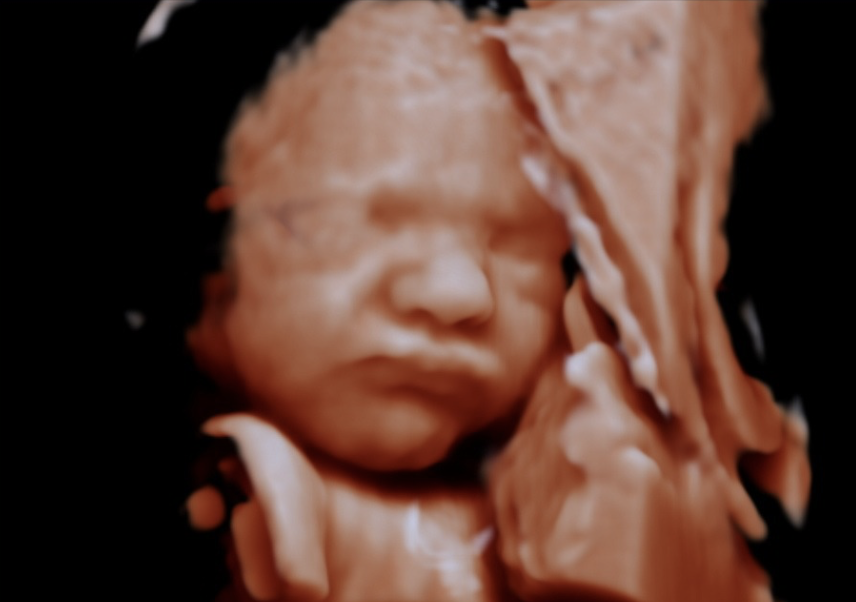

Fem Jordmødre is a private midwifery center where I offer ultrasound examinations throughout pregnancy—no referral needed. While the name originally reflected a collaboration of five midwives, the practice is now run solely by me—an experienced and dedicated midwife with extensive expertise in ultrasound imaging. My goal is to provide you with a professional examination in a calm and reassuring environment.